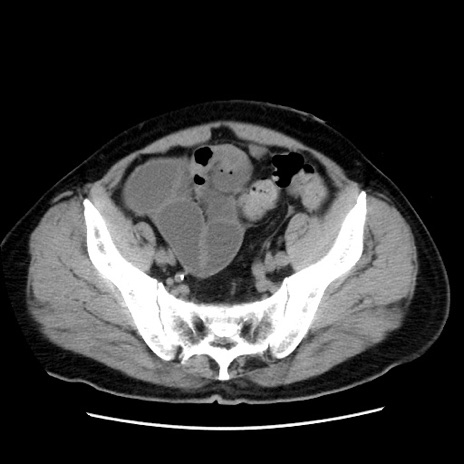

冠状断像